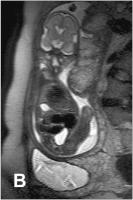

Abbildung 4: Fetus in der 32. SSW mit linksseitiger kongenitaler Zwerchfellhernie, koronale Schichtführung. Mit Hilfe der hier verwendeten Kontrastparameter können intrathorakal mit Mekonium gefüllten Darmanteile sehr hell dargestellt werden. Die Leber, sie ist etwas weniger hell als Mekonium, liegt intrabdominal. Am Hals ist auch die Glandula thyroidea zu erkennen.